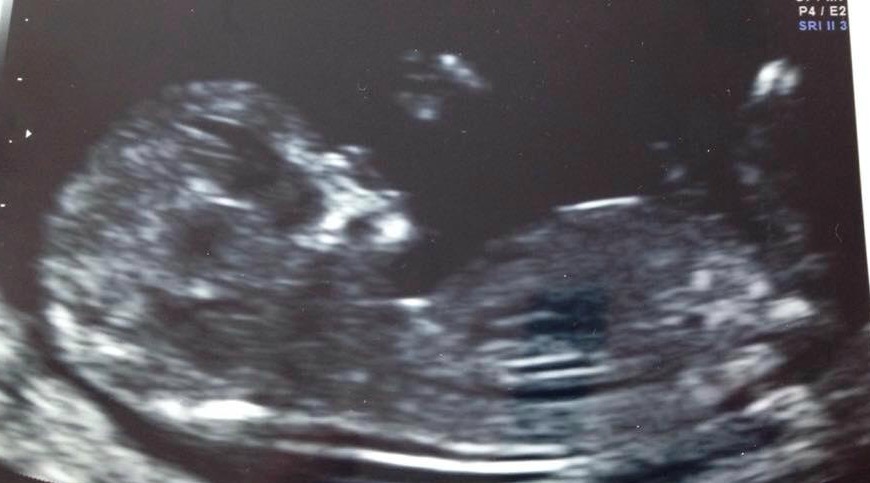

I'd love your opinions for my friend please :) She is 12+4.

I am going to say girl, but I am still new to this.

Kinda hard to tell slight girl lean!

Maaaybe girl? Not clear though.

Girl

Girly but not a clear nub